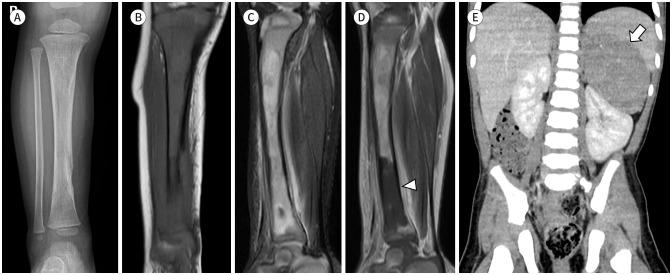

MRI plays a crucial role in bone marrow (BM) assessment, and has very high sensitivity in diagnosing marrow disorders. However, for radiologists who may not frequently encounter pediatric imaging, distinguishing pathologic BM lesion from normal BM can be challenging. Conditions involving the BM in pediatric patients, such as leukemia and metastatic neuroblastoma, often manifest with diverse musculoskeletal symptoms and may be diagnosed using musculoskeletal MRI examinations. Accurate interpretation of pediatric MRI requires not only an understanding of the normal composition of BM but also an awareness of agerelated developmental changes in the marrow and familiarity with conditions that commonly involve pediatric BM. We aim to describe the composition of normal BM and outline the normal and abnormal MRI findings in pediatric BM. Additionally, we aim to present clinical cases of malignant BM disorders including leukemia, neuroblastoma metastasis, and other malignant BM disorders.

磁共振成像(MRI)在骨髓(BM)评估中起着至关重要的作用,并且在诊断骨髓疾病方面具有很高的敏感性。然而,对于可能不经常接触儿科影像的放射科医生来说,区分病理性骨髓病变与正常骨髓可能具有挑战性。儿科患者中涉及骨髓的疾病,如白血病和转移性神经母细胞瘤,通常表现为多样的肌肉骨骼症状,可通过肌肉骨骼MRI检查进行诊断。准确解读儿科MRI不仅需要了解骨髓的正常组成,还需要认识到骨髓中与年龄相关的发育变化,并熟悉常见累及儿科骨髓的疾病。我们旨在描述正常骨髓的组成,并概述儿科骨髓的正常和异常MRI表现。此外,我们旨在展示包括白血病、神经母细胞瘤转移和其他恶性骨髓疾病在内的恶性骨髓疾病的临床病例。